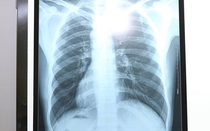

Bệnh nhân nam nhập viện trong tình trạng đau tức hậu môn. Qua X Quang và nội soi, các bác sĩ phát hiện, dị vật đã chui sâu vào trong trực tràng của người đàn ông khoảng 10cm rất khó lấy ra.

Dị vật bị tụt sâu vào trực tràng khiến bệnh nhân không thể lấy ra.